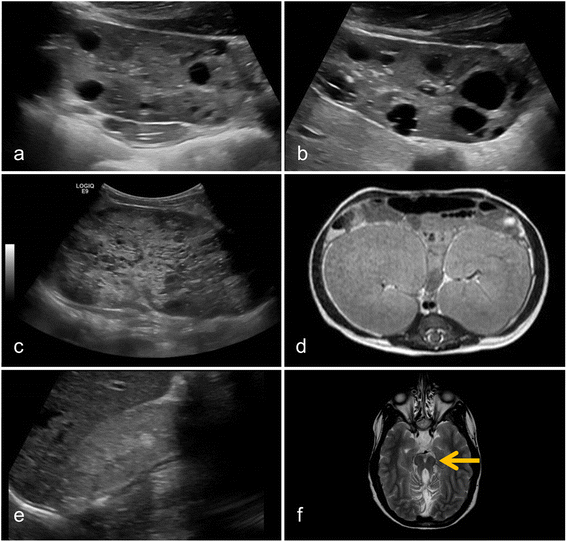

Figure 2

Typical radiological findings in children with cystic kidney disease. (a, b) Typical ubiquitous macrocysts and enlarged kidney volumes are found a 15-year-old boy with ADPKD. (c) ARPKD typically presents with hyperechogenic kidney with microcysts as shown in a sonography of a 1-year-old boy. (d) The massively enlarged kidney volume in ARPKD is illustrated on axial abdominal MRI of a 10-month-old girl. (e) Ultrasonography of patients with nephronophthisis often shows small, hyperechogenic kidneys without corticomedullar differentiation. If present, cysts are typically found at the corticomedullar border. (f) Cerebellar vermis asplasia and elongated superior cerebellar peduncles result in the Molar Tooth Sign on axial MRI, which is pathognomonic for Joubert syndrome. ADPKD, autosomal dominant polycystic kidney disease; ARPKD, autosomal recessive polycystic kidney disease.